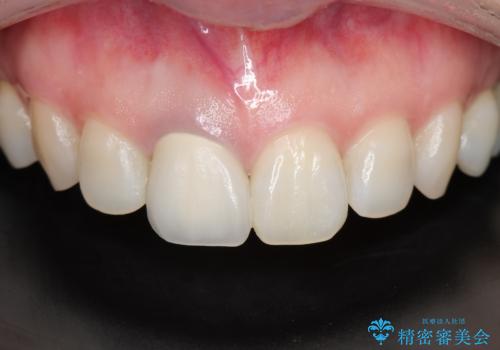

問題なく綺麗な被せ物が入りました。

保険の被せ物は安価ですが劣化しやすいため着色しやすい素材です。

セラミックの素材は劣化することなくまた虫歯の再発のリスクも下げてくれます。